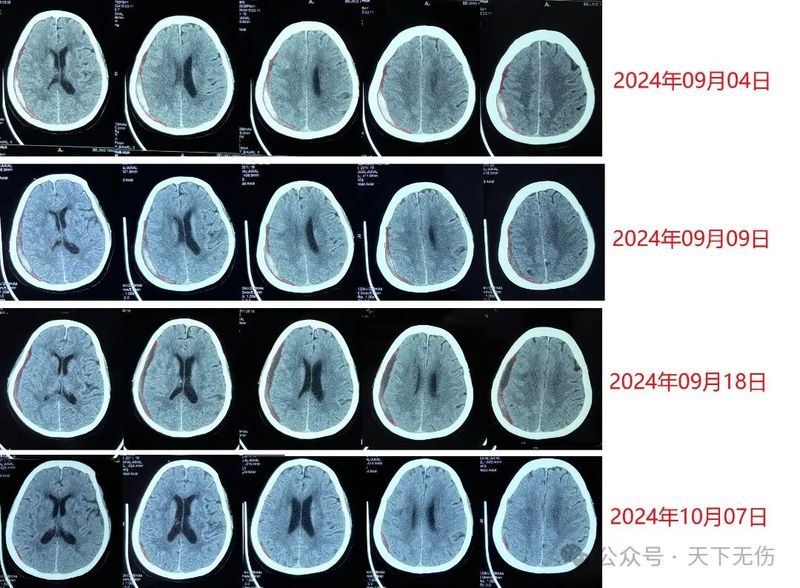

希望我的治療方案盡快普及

董世英的科普號(hào)2024年10月21日245